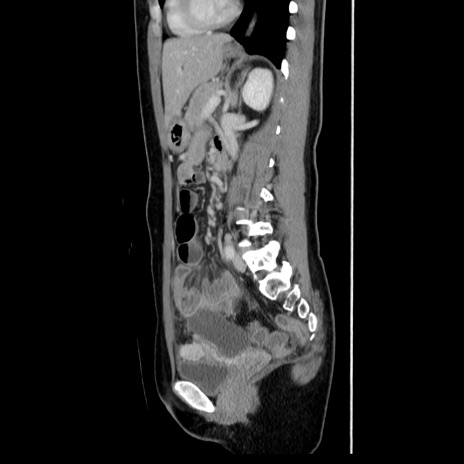

症例39(矢状断像)

【症例】40歳代女性

【主訴】上下腹部痛

【現病歴】2日目から下腹部痛あり。夜間は痛みで眠れなかった。昨日より上腹部痛と下痢が出現。臥位で痛みは軽快したため、休んでいた。本日になって臥位でも立位でも痛みが強くなってきたため救急要請。

【既往歴】子宮内膜症

【身体所見】部:平坦・軟、左上下腹部に圧痛あり、反跳痛あり。

【データ】WBC 21800、CRP 26.78

CT